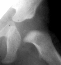

A ten year old female presented with a left hip dislocation. She was born by Cesarean-section because of slow progression of labor. The child was not breech and was noted to have a dislocatable hip at birth. There was a negative family history of DDH. An X-ray prior to application of the brace showed the dislocation of the hip. The patient was first seen at AIDI on 9th day. Abduction of the right hip was 80 degrees but left was only 60 degrees. There was a positive Galeazzi sign with the left hip being shorter than the right. X-rays showed a left hip dislocation and right hip subluxation . A Pavlik harness was applied. After two months, the right hip improved but the left hip was still dislocatable. For this, home traction was started. Even after 2 months, the left hip did not reduce. Therefore, an arthrogram, adductor tenotomy and closed reduction was done at 4 months of age. Single hip spica was applied with the hip in 40 abduction and 100 flexion. Eight weeks later an arthrogram was performed and the cast was reapplied with the hip in 35 degrees abduction and 100 degrees flexion.

Four months later, the spica cast was removed and an Atlanta brace was applied. X-rays showed avascular necrosis at ten months of age . At two years of age, the ossification of the left nucleus was still delayed. The leg lengths were equal and the range of motion of the hip was full.

The progression of the hip is documented by x-rays taken at 1 year of age, 2 years of age, 3 years of

age, 5 years of age, 7 years of age, then at ten years of age, early closure of the lateral portion of proximal growth plate observed. Coxa valga was also observed.